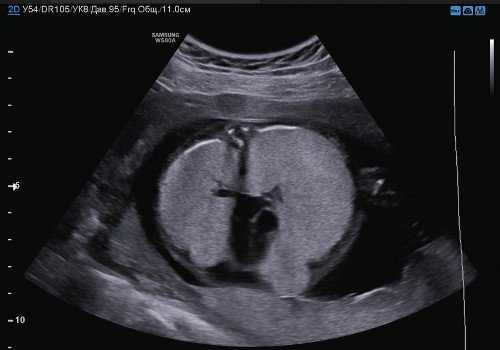

Последний, 7 случай был у женщины 38 лет, которая беременна впервые без тягостного акушерско-гинекологического анамнеза. Сканирование в первом триместре было нормальным и комбинированный скрининг также показал низкий уровень риска хромосомных аномалий. Диагноз ВОДП был обнаружен на сроке беременности 21 неделя за счет генерализованного отека кожи в 15 мм и асцита у плода (рис.3). На УЗИ визуализация трахеи была нормальной, диаметром в 3 мм. Кроме того, наблюдаем нормальный вид голосовых связок, которые периодически двигались в просвет гортани (рис.4). Тем не менее, ни одного движения жидкости через трахею при допплеровском сканировании не удалось обнаружить. Полное сканирование плода с помощью ультразвука и магнитно-резонансной томографии исключило другие сопутствующие аномалии плода. Фетометрия отвечала гестационному возрасту плода, кариотип был 46XX. После консультаций и принятий местного комитета по этике, родители дали информированное согласие на проведение фетоскопической коррекции патологии.

Рис.3. ВОДП на сроке беременности 21 неделя. Массивное двустороннее расширение легких с повышенной эхогенностью, перевернутым куполом диафрагмы (а, b), асцит тяжелой стадии (c), дилатация дыхательных путей (d).

Рис.4. Тот же плод. Нормальный вид голосовых связок, наблюдаем их периодическое открытие (а) и закрытия (б).